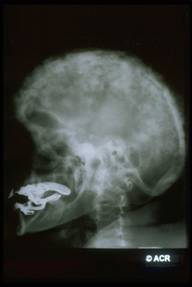

Anomalie scheletriche :

- tibia a sciabola

- ingrossamento del cranio

- interessamento del rachide con perdita dell'altezza (cifosi o scoliosi) e stenosi spinale

Reperti radiografici

Lisi ossea: riflette l'aumentata attività osteoclastica;

Sclerosi: riflette l'aumentata attività osteoblastica;

Aumento volumetrico dell'osso;